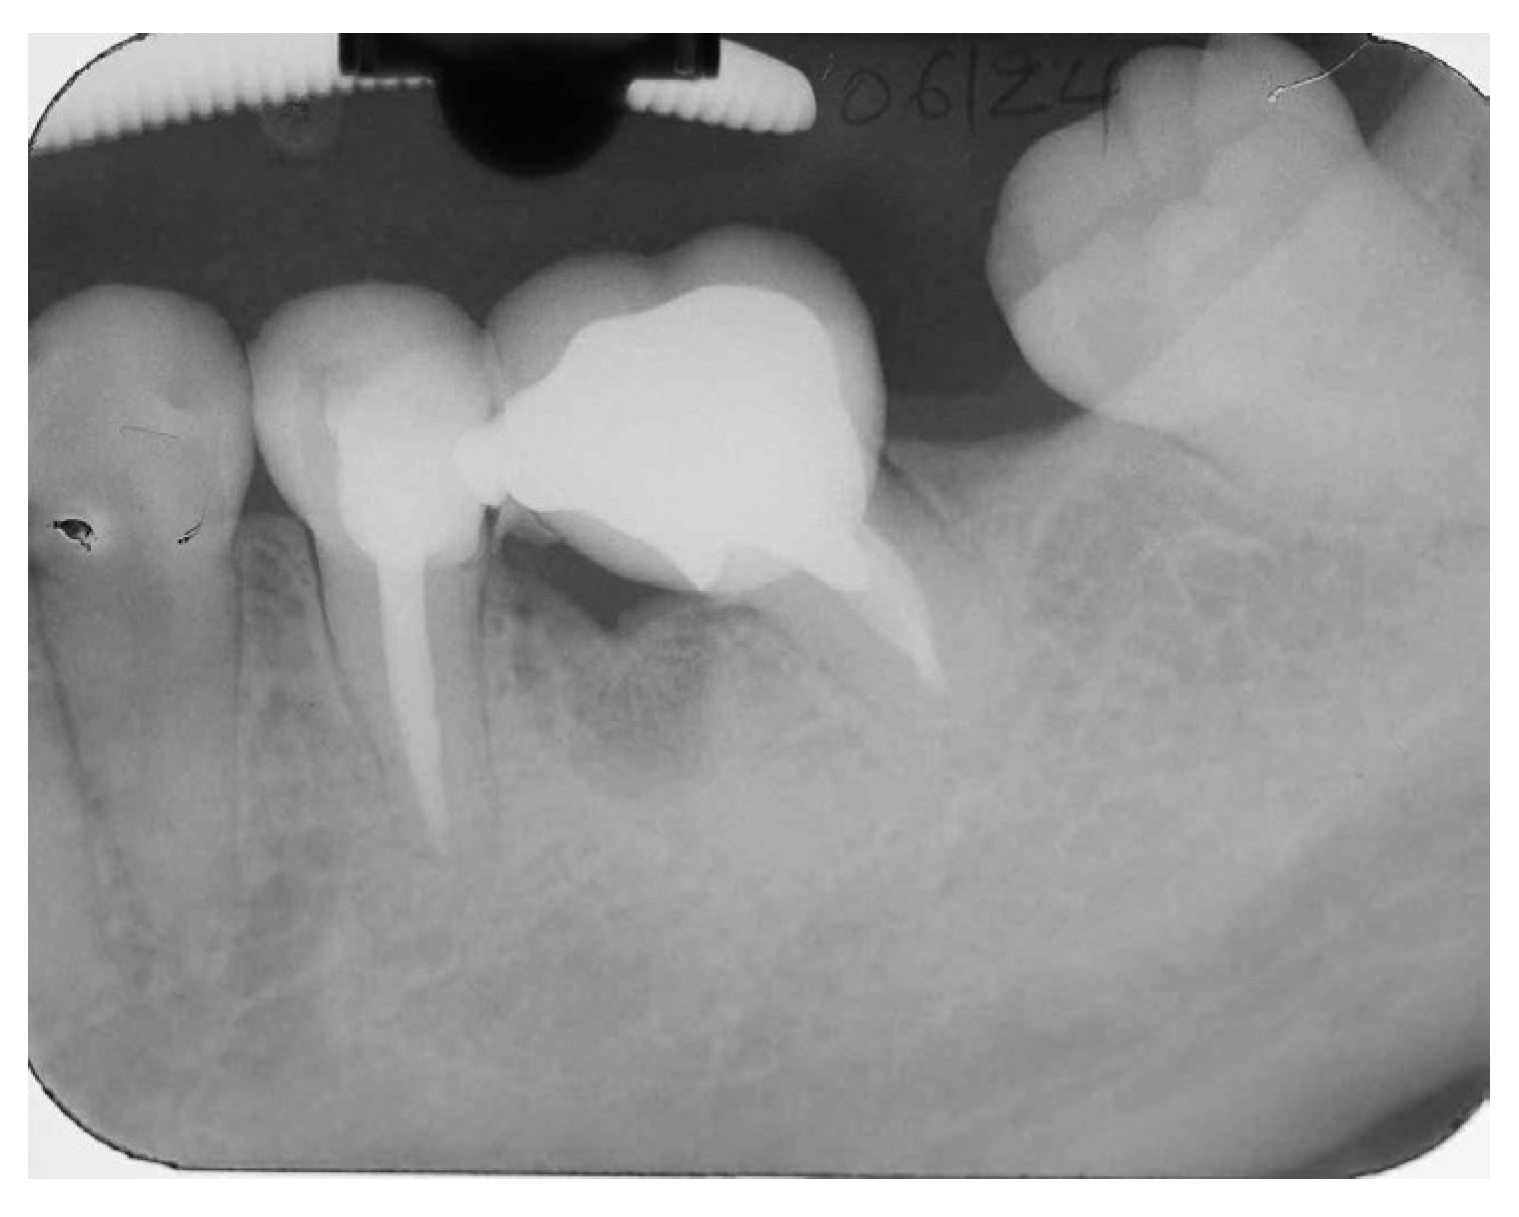

A 55-year-old female patient with no contributory medical history and non-smoker referred by a periodontologist to our clinic for endodontic evaluation and if possible, retreatment of the mesial root of the lower left first molar. According to referring records and as it was indicated in the accompanying periapical radiograph (Figure 15), the initial treatment plan included removal of the distal root of tooth #36. Study of the periapical radiograph showed a furcal involvement in the tooth #36 and a periapical lesion of the untreated distal root. Clinical investigation revealed a type III furcation involvement, first grade mobility combined with deep periodontal pocket in the furcation area while the presence of initial caries was detected at the distal margins of the porcelain fused to metal crown. Based on these findings, removal of the crown was a necessity in order to examine if the tooth crown was restorable. As shown in Figure 16, a periapical radiograph taken after removal of the crown revealed the presence of caries in the disto-buccal part of the tooth and the existence of two distal roots having a furcal involvement in between them.

Figure 15. Initial Periapical X-Ray.